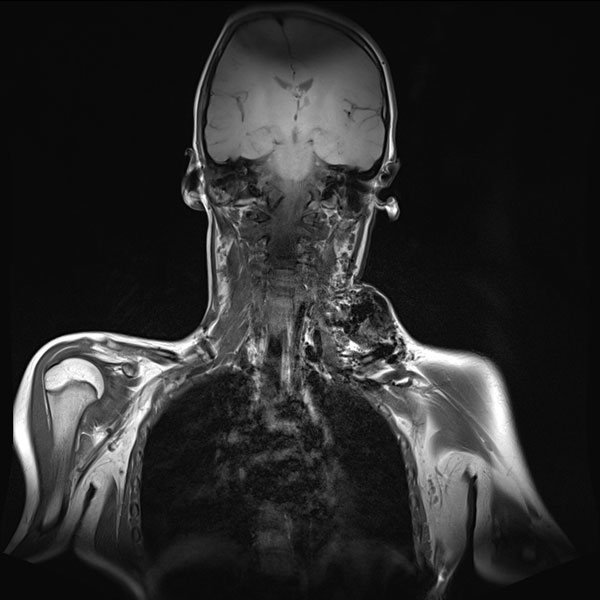

In der nativen, T1-gewichteten, koronaren MRT zeigt sich die arteriovenöse Malformation als stark hypointense Raumforderung ohne eigentlich soliden Charakter. Das fehlende MRT-Signal ist durch den schnellen und starken Durchfluss bedingt (sogenannte „Flow-voids“). Das Blut strömt hier so schnell durch die Läsion, dass es kein signalgebendes Echo erzeugen kann.